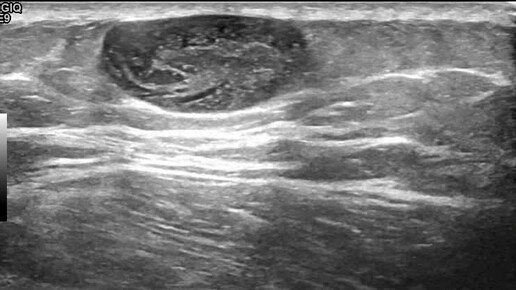

Видео к статье "Подкожная атерома мягких тканей бедра" https://dzen.ru/a/Zv0GGyWGPxTvhV4H

Ультразвуковые находки от врача УЗД Зорина Я.П.